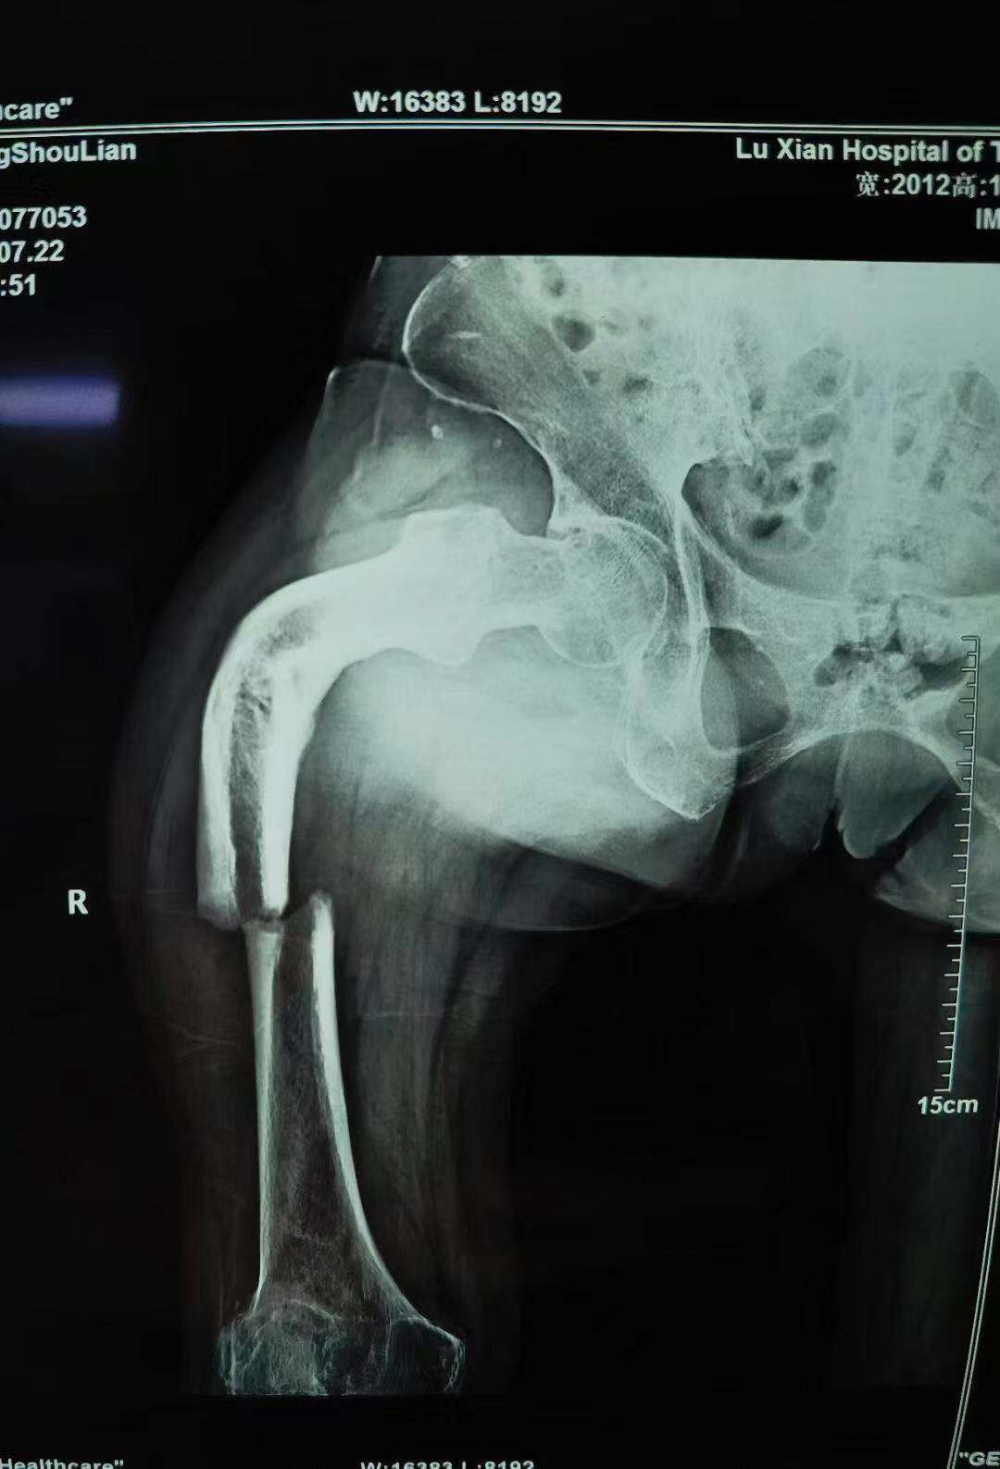

当她的X光片出来时,收治的医生都被她的伤情吓了一跳。原来此次她骨折的上端还有一处骨伤畸形愈合。这是什么情况呢?

原来张守莲在三年前还摔伤过一次,当时在一家医院进行了手法复位,但因操作不当,没能复位成功,留下了后遗症。三年来她都是以拄拐行走。

据泸州市中医院骨伤一科主任汪永泉介绍张女士的病情较为复杂,三年的时间导致神经组织、血管等都已经适应畸形以后的状态。